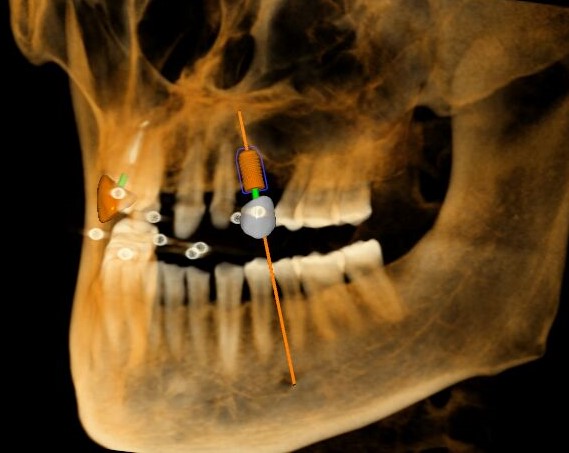

三維視圖

根據(jù)患者CT顯示,使用種植導(dǎo)航軟件設(shè)術(shù)前手術(shù)方案??紤]到患者拒絕手術(shù)摘除上頜竇囊腫等因素,此次手術(shù)選用了Straumann骨水平4.10*8.0mm的植體,植體末端位點(diǎn)設(shè)計(jì)距上頜竇底壁2mm處的同時(shí)兼顧種植方向和修復(fù)間隙,來(lái)達(dá)到理想的效果。

從術(shù)后CBCT顯示可以看出,手術(shù)操作中完美地避開(kāi)上頜竇底,并兼顧了正確的種植方向和修復(fù)間隙